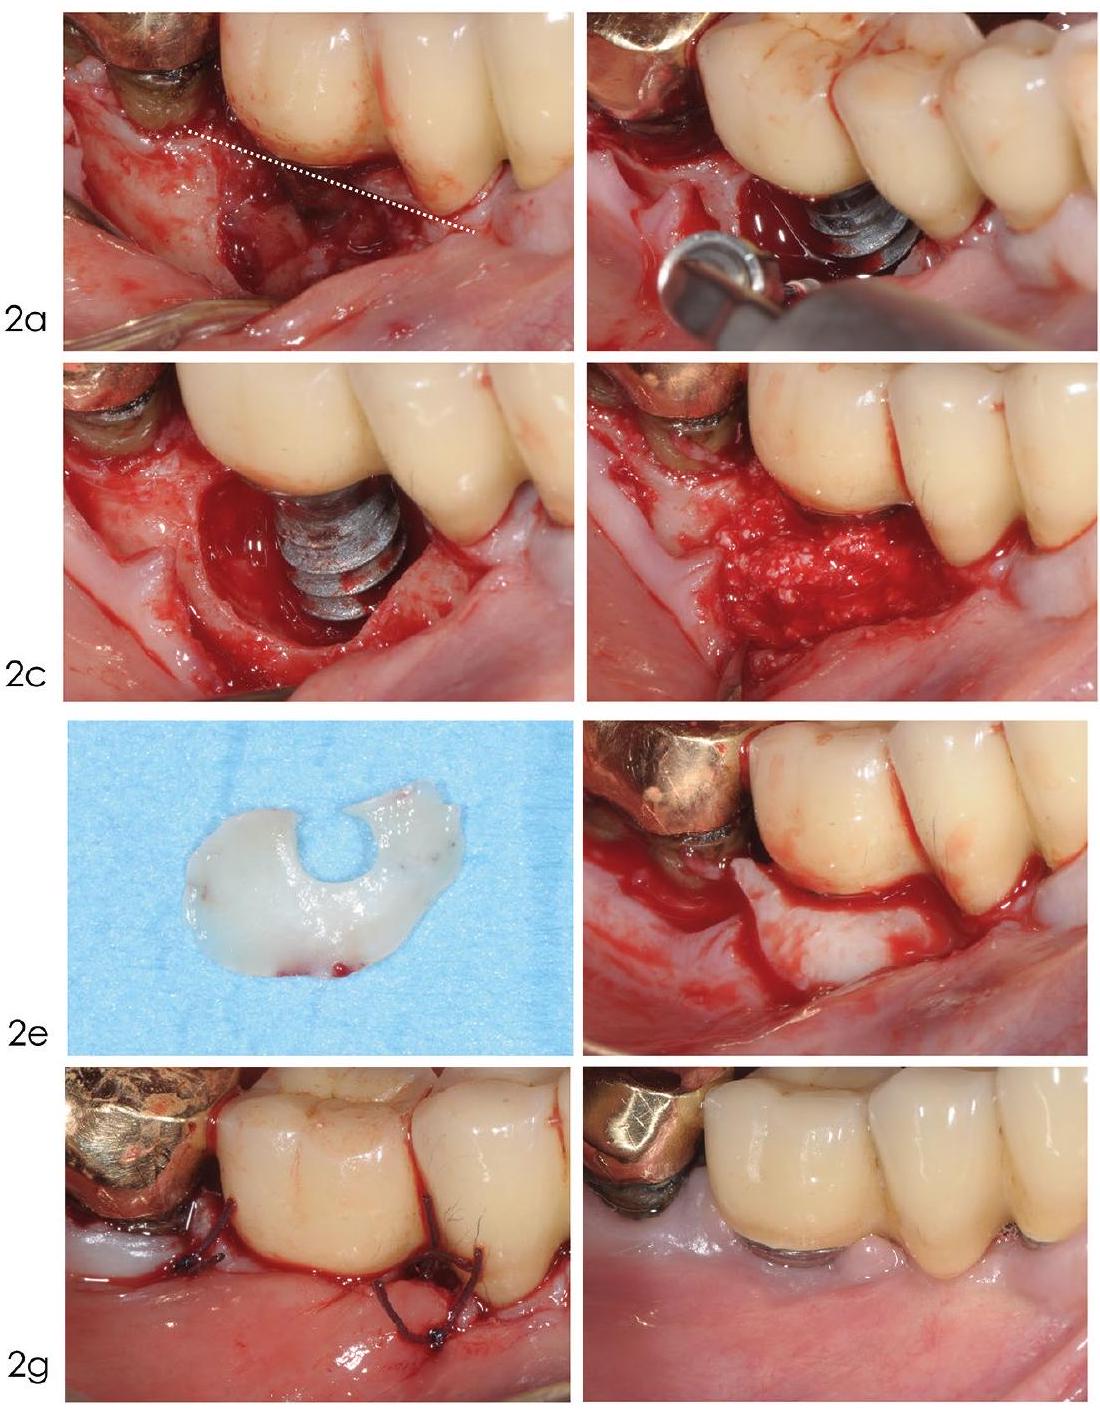

Access flap debridement without resective procedures

is decontaminated using mechanical, chemical, and potentially other adjunctive methods such as photodynamic therapy or laser treatment. The flap is then repositioned and sutured in place.

Access flap debridement with resective procedures

Comparative studies have evaluated the efficacy of implantoplasty against alternative decontamination with air-polishing with glycine powder.

- Deep and narrow defects are more favourable for the stabilisation of the graft and the consequent formation of new bone

- The extension of the full-thickness flap should be planned carefully, balancing the aim to minimise the invasiveness of the procedure and the need to have access to the bottom of the defect

- The regenerative biomaterial should be selected on the basis of proper scientific validation and applied without overfilling the defect

- The graft should be inserted only after complete elimination of the granulation tissue and the decontamination of the implant surface

- In case of insufficient keratinised mucosa width, a connective tissue graft should be trimmed and adapted over the entire defect so as to cover

of the surrounding alveolar bone to ensure stability of the graft material. Should the defect be circumferential in an area with no keratinised mucosa, a large connective tissue graft could be punched, by means of a circular blade, and adapted circumferentially around the defect - Patients should be instructed on how to protect, care for, and keep clean the surgical

site so as to favour primary healing of the surgical wound.